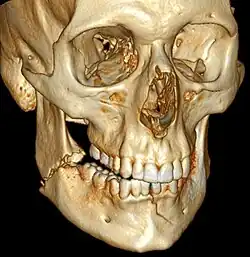

| 3D computed tomographic image of a mandible fracture in two places. One is a displaced right angle fracture and the other is a left parasymphyseal fracture. | |

Mandibular fracture, also known as fracture of the jaw, is a break through the mandibular bone. In about 60% of cases the break occurs in two places.[1] It may result in a decreased ability to fully open the mouth.[1] Often the teeth will not feel properly aligned or there may be bleeding of the gums.[1] Mandibular fractures occur most commonly among males in their 30s.[1]

Mandibular fractures are typically the result of trauma.[1] This can include a fall onto the chin or a hit from the side.[1] Rarely they may be due to osteonecrosis or tumors in the bone.[1] The most common area of fracture is at the condyle (36%), body (21%), angle (20%) and symphysis (14%).[1] Rarely the fracture may occur at the ramus (3%) or coronoid process (2%). While a diagnosis can occasionally be made with plain X-ray, modern CT scans are more accurate.[1]

Computed tomography is the most sensitive and specific of the imaging techniques. The facial bones can be visualized as slices through the skeletal in either the axial, coronal or sagittal planes. Images can be reconstructed into a 3-dimensional view, to give a better sense of the displacement of various fragments. 3D reconstruction, however, can mask smaller fractures owing to volume averaging, scatter artifact and surrounding structures simply blocking the view of underlying areas.